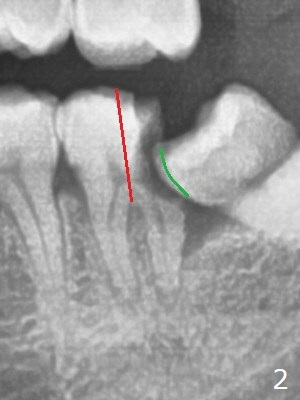

A 36-year-old man with poor dentition (smoker 1/4 ppd) requests extraction of sympto-matic teeth (#18 and 32, Fig.1). A half of Osteogen Plug is placed at #32 post extraction. To extract #18, the tooth has to be sectioned (Fig.2 red). The mesial portion is removed easy, while the distal one requires removing the mesial surface of #17 (Fig.2 green). Vanilla bone is placed after extraction (Fig.3), covered by 8x8 mm Amnion-Chorion Allograft and sutured with 4-0 PGA. Four months later, the mesial surface of #17 will be trimmed (Fig.4 black area) so that surgical guide metal sleeve (green) will be seated in the neutral position of the edentulous area. After extraction (Fig.5 black), the distal portion of the mesial crest will be resorbed, leading to gingival papilla atrophy and food impaction (Fig.6). Keeping the mesial portion of the root (Fig.7 *, socket shield) is able to prevent mesial crestal bone loss. The immediate implant will be placed ~ 2 mm short of the depth and checked whether it touches the retained root or not.